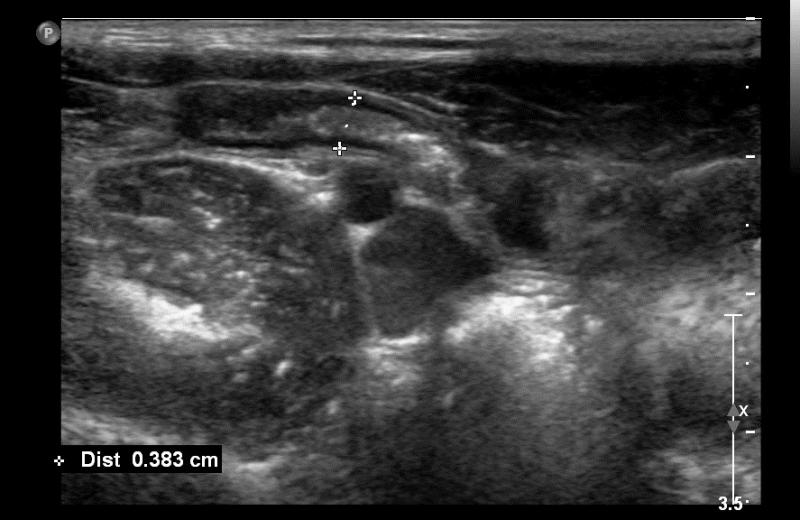

Przypadek 48: 8-letni pacjent z bólami brzucha Rozpoznanie: W badaniu usg uwidoczniono prawidłowy wyrostek robaczkowy (zaznaczony markerami).